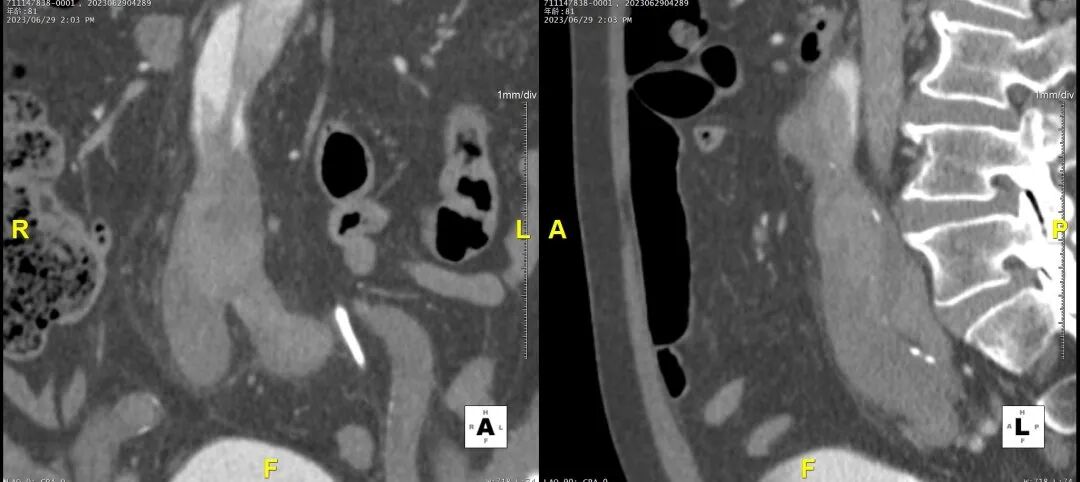

病例CTA详解

横断面影像

1)内膜多处撕裂,真腔严重狭窄。

2)CA假腔供血,SMA双腔供血,LRA假腔供血,RRA真腔供血,腹主段闭塞。

3)LSA起始部平均直径43mm+,降主段多发破口,真腔狭窄。